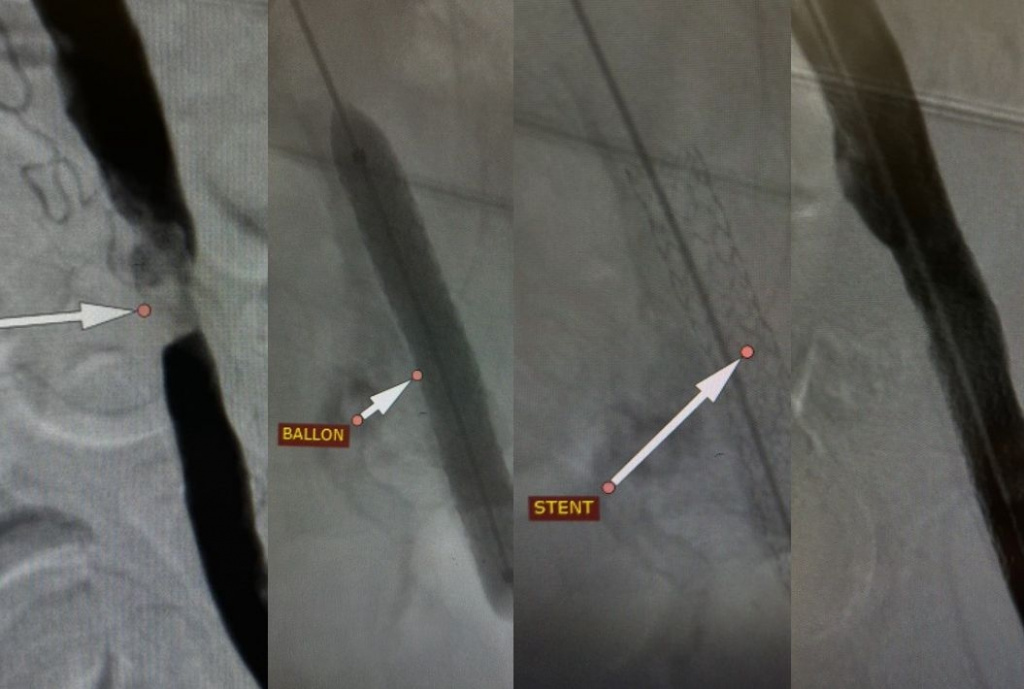

Процедуру медики провели под местной анестезией. Через небольшой прокол в бедренной артерии врачи ввели мужчине специальный баллонный катетер, который под контролем рентгена довели до суженного участка подвздошной артерии.

Баллон расширили, восстановили просвет сосуда, а затем для надежности установили металлический каркас - стент, который не дает артерии сужаться вновь.

- Мы выполнили стентирование подвздошной артерии, которое позволило быстро нормализовать кровообращение в нижней конечности. Уже спустя сутки пациент смог самостоятельно передвигаться и покинул стационар с рекомендациями для дальнейшего восстановления здоровья, - пояснили медики.

Облздрав, на фото сужение артерии ноги до операции и артерия после